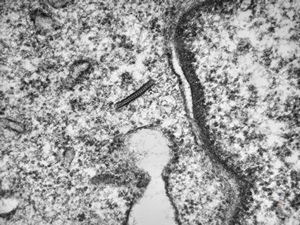

M, 43y. | myeloid leukemia … Auer bodies